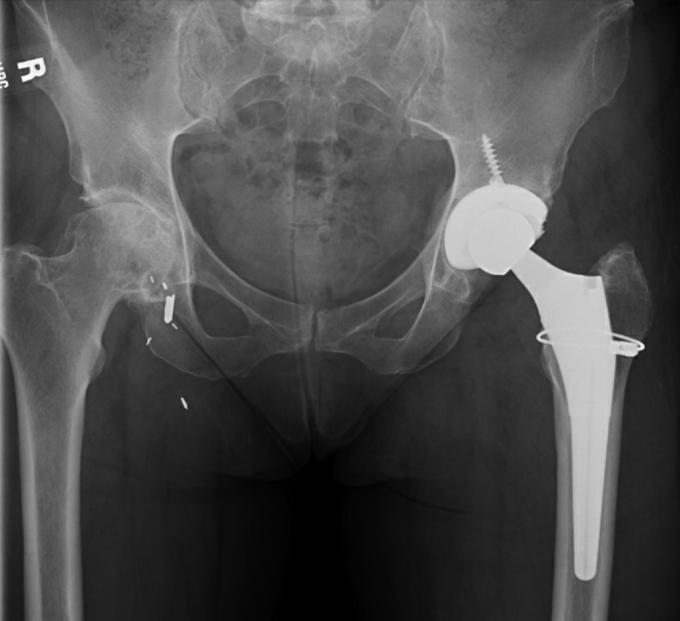

Adverse local tissue reactions secondary to mechanically assisted crevice corrosion (MACC) at the trunnion is a complication of total hip arthroplasty known to cause local soft-tissue damage. However, what is not as well appreciated is that MACC in metal-on-polyethylene (MOP) articulations can lead to cobalt ion serum elevations with associated neurological dysfunction just as in metal-on-metal articulations. We report a compelling case for the association of neurologic dysfunction tied to metal ion elevations secondary to MACC at two distinct MOP tapers in a 58-year-old intensive care unit nurse with two hips implanted 3 years apart. This report further raises awareness about the potential of MACC-generated elevated ion levels to produce neurological symptoms that might otherwise be overlooked in patients with MOP articulations.

继发于机械辅助缝隙腐蚀(MACC)的局部组织不良反应发生在股骨柄处,是全髋关节置换术的一种并发症,已知会导致局部软组织损伤。然而,人们尚未充分认识到的是,金属对聚乙烯(MOP)关节中的MACC会导致血清钴离子升高,并伴有神经功能障碍,就如同金属对金属关节一样。我们报告了一例令人信服的病例,一名58岁的重症监护病房护士,其双侧髋关节分别在3年前植入,在两个不同的MOP锥度处,继发于MACC的金属离子升高与神经功能障碍有关。本报告进一步提高了人们对MACC导致离子水平升高从而产生神经症状的可能性的认识,否则这些症状在MOP关节患者中可能会被忽视。